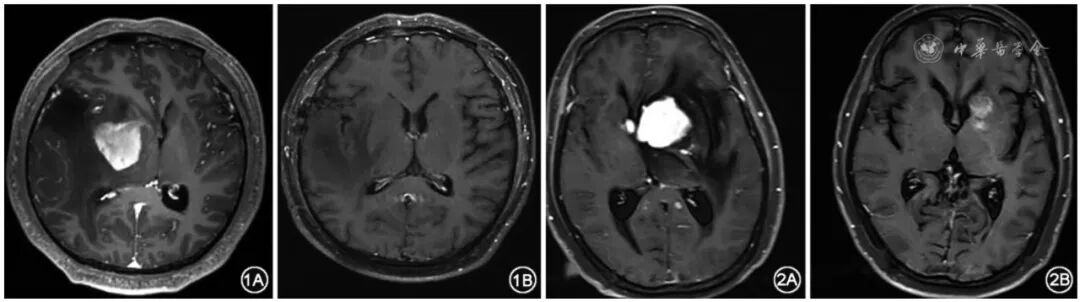

18例患者肿瘤完全缓解1例,部分缓解16例,疾病稳定1例。典型病例的影像学图像见图1、2。

图1 危重症原发性中枢神经系统淋巴瘤患者(例5)化疗前后MRI图像:患者入院时卡氏功能状态(KPS)评分60分,化疗前脑中线偏移严重(1A);1个疗程化疗后肿瘤部分缓解,中线复位(1B)

图2 危重症原发性中枢神经系统淋巴瘤患者(例7)化疗前后MRI图像:入院时浅昏迷,KPS评分20分,化疗前脑中线移位,组织水肿明显(2A);1个疗程化疗后肿瘤部分缓解,中线复位(2B)